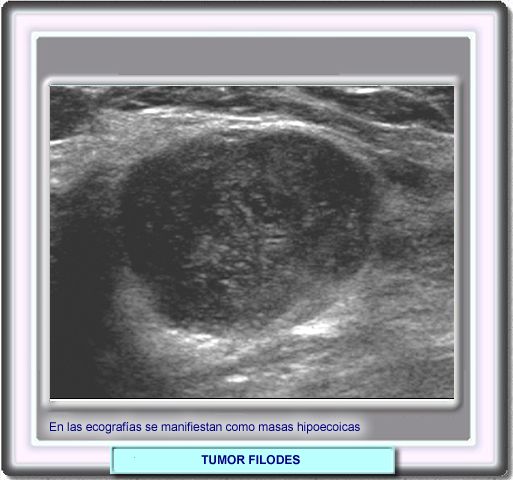

La ecografía muestra nódulos o masas hipoecoicas con contornos delimitados. Ocasionalmente pueden observarse espacios quísticos. En la mayor parte de los casos, los tumores filodes de asemejan a los fibroadenomas